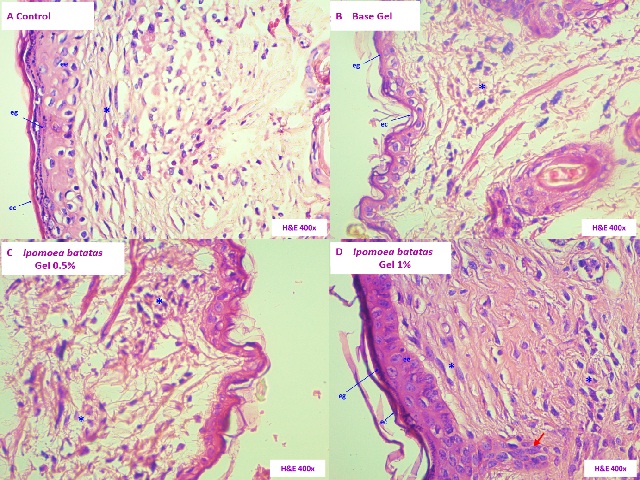

ArticleViewAbstractPharmacognosy Journal,2021,13,6s,1720-1726.DOI:10.5530/pj.2021.13.222Published:December 2021Type:Research ArticleEffect of a Gel Based on Ipomoea batatas (Purple Sweet Potato) on Dermal Wound Healing in MiceCarmen R. Silva-Correa, Cristel M. Ortiz-Noriega, Víctor E. Villarreal-La Torre, Abhel A. Calderón-Peña, Cinthya L. Aspajo-Villalaz, Luz M. Guerrero-Espino, William A. Sagástegui-Guarniz, Anabel D. González- Siccha, María V. González-Blas, José L. Cruzado-Razco, Jorge Del Rosario-Chávarri, Patricia Contreras- Vera, and Julio Hilario-Vargas Carmen R. Silva-Correa1,*, Cristel M. Ortiz-Noriega1, Víctor E. Villarreal- La Torre1, Abhel A. Calderón-Peña2, Cinthya L. Aspajo-Villalaz2, Luz M. Guerrero-Espino3, William A. Sagástegui-Guarniz1, Anabel D. González-Siccha1, María V. González-Blas1, José L. Cruzado- Razco1, Jorge Del Rosario- Chávarri2, Patricia Contreras-Vera4, Julio Hilario-Vargas3 1Facultad de Farmacia y Bioquímica, Universidad Nacional de Trujillo, PERÚ. 2Facultad de Ciencias Biológicas, Universidad Nacional de Trujillo, PERÚ. 3Facultad de Medicina, Universidad Nacional de Trujillo, PERÚ. 4Hospital Víctor Lazarte Echegaray, Trujillo, PERÚ. Abstract:Background: Ipomoea batatas (L.) Lam. (I. batatas) is a root native from South America that is characterized by its antioxidant, antimicrobial and anti-inflammatory properties. These properties contribute to the wound healing process. Objective: To evaluate the healing activity of a gel based on I. batatas on dermal wound healing in mice. Material and methods: An acid ethanolic extract (1.5 N hydrochloric acid: Ethanol 96 ° 15:85, v / v) was prepared with the peels of the roots of I. batatas "purple sweet potato", which was incorporated into the formulations 0.5% and 1% gel. Mus musculus Balb / c with induced injury were distributed in four experimental groups: Group I (Control), which did not receive any treatment. Group II (Gel base), Group III (Gel I. batatas 0.5%) and Group IV (Gel I. batatas 1%) received the daily administration of topical treatments for 14 days. Wound closure was determined during the experimentation time, then they were euthanized with sodium pentobarbital 60 mg / kg / pc v.ip. to obtain skin samples for histopathological analysis. Results: Group IV shows a higher percentage of wound closure, which is also evidenced in histopathological changes. Conclusions: The 1% gel based on the ethanolic extract of the peels of the roots of Ipomoea batatas (L.) Lam. they show healing activity in wounds induced in mice, being the most effective treatment. Keywords:Histology, Ipomoea batatas, Skin., Wound HealingView:PDF (5.04 MB) PDF Images Histopathological sections of the skin of Mus musculus Balb / c. A. Group I (Control). B. Group II. (Base Gel). C. Group III (Gel I. batatas 0.5%). D. Group IV (Gel I. batatas 1%). Keratinous stratum corneum (ec), stratum granulosa (eg), stratum spinosum (ee), basal cells (eb) dermal papillae (arrow), fibroblasts (*), sweat glands (gs), eschar (s). (Hematoxylin and Eosin stained, 400X). ‹ In silico Study on the Promising Active Components of Terpenoid and Fucoidon from Sargassum sp. in Inhibiting CGRP and TNF-α up Effect of a Gel Based on Ipomoea batatas (Purple Sweet Potato) on Dermal Wound Healing in Mice ›